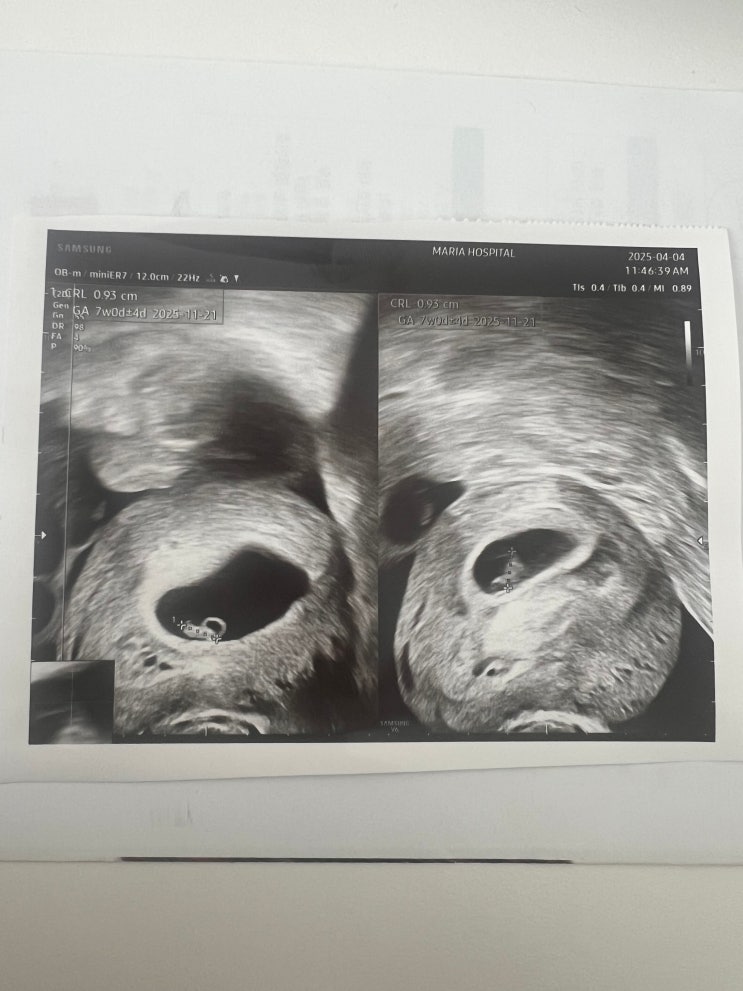

21. [신선2차] 쌍둥이 심장소리 듣는날 (4/4, 7주0일)

한주동안 개쫄은 상태로 지내다가 병원가는날. 밤마다 생리통 증상처럼 아랫배가 싸르르 아프고 콕콕 쑤시...